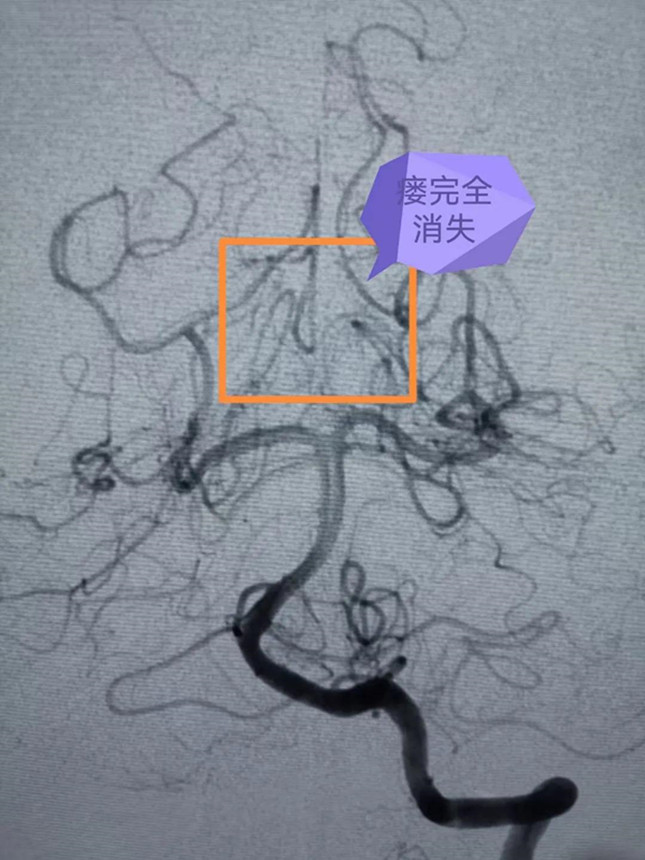

专家团队在大梅的大腿根部股动脉穿入笔芯粗细的导管,然后在脑血管造影机的X线引导下,将一米多长的细若发丝的微导管通过血管小心翼翼送至脑血管畸形部位,由于血管畸形位于脑深部,供血动脉迂曲细长,角度刁钻,手术困难极大,但是专家团队小心仔细,锲而不舍,经过5个多小时的紧张手术,最终将脑血管畸形完全栓塞。手术后,大梅的脑部畸形团块消失,恢复良好。

潘剑威主任医师介绍,脑血管介入是目前医学领域最先进的脑血管疾病诊断治疗方法之一,创伤小、恢复快,随着设备、材料、技术的不断进步,越来越多的脑血管疾病可以通过脑血管介入得到诊治。但同时,脑血管介入对手术医生的技术、心力、脑力和体力都有极高的要求。浙大一院神经外科介入团队经过十余年的发展,已经成为浙江省领先、全国一流的神经介入团队。